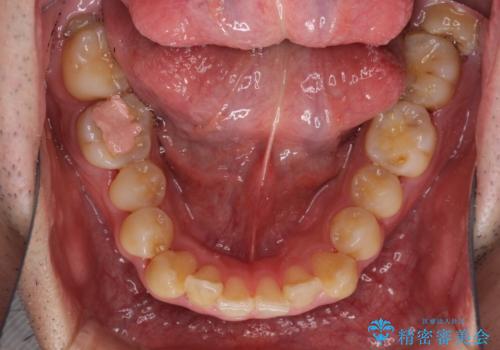

前歯のクロスバイトを改善 インビザラインによる矯正治療

- 前歯のクロスバイトを気にして来院された患者様です。

デコボコやクロスバイトが散見されたため、IPR(歯と歯の間を削る)によってスペースを獲得できるように設計し、インビザラインにより治療を行うこととしました。

今回は、ワイヤー装置を併用することなく治療を行い、トラブルなく、満足のいく歯列に整えることができました。

矯正治療の途中でホームホワイトニングを併用され、術前とは見違えるほどきれいな口元となりました。